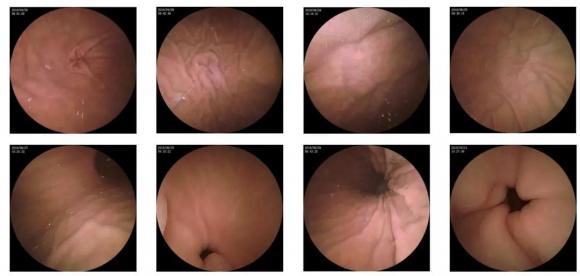

10—15分鐘即可完成賁門(mén)、胃底、胃體、胃角、胃竇、幽門(mén)等解剖部位觀察,讓胃部檢查更高效。更為重要的是,檢查全程無(wú)痛、無(wú)創(chuàng)、無(wú)麻醉,避免了傳統(tǒng)插管胃鏡帶來(lái)的生理痛苦。

二、高清圖像,精確診斷

膠囊機(jī)器人的專(zhuān)利三鏡片鏡頭,可深入觀察0.04毫米微小單位,每秒可拍高達(dá)4張高清醫(yī)學(xué)照片。

醫(yī)生通過(guò)智能閱片系統(tǒng),可自動(dòng)對(duì)海量圖像識(shí)別過(guò)濾,智能篩選,能有效提升醫(yī)生檢查及閱片效率。

任何細(xì)微的胃部病變,如胃潰瘍、胃出血、息肉等都無(wú)所遁形,盡在大圣磁控膠囊式內(nèi)窺鏡系統(tǒng)的掌握之中。